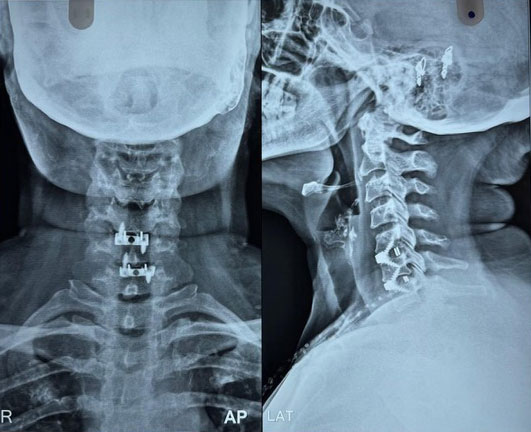

Dr. Ujwal Yeole is an experienced neurosurgeon specializes in treating a wide spectrum of neurological conditions including neuro-oncology, peripheral nerve disorders, vascular disorders, spinal pathologies, pediatric neurosurgery, neuro-trauma and skull base neuroendoscopic procedures.